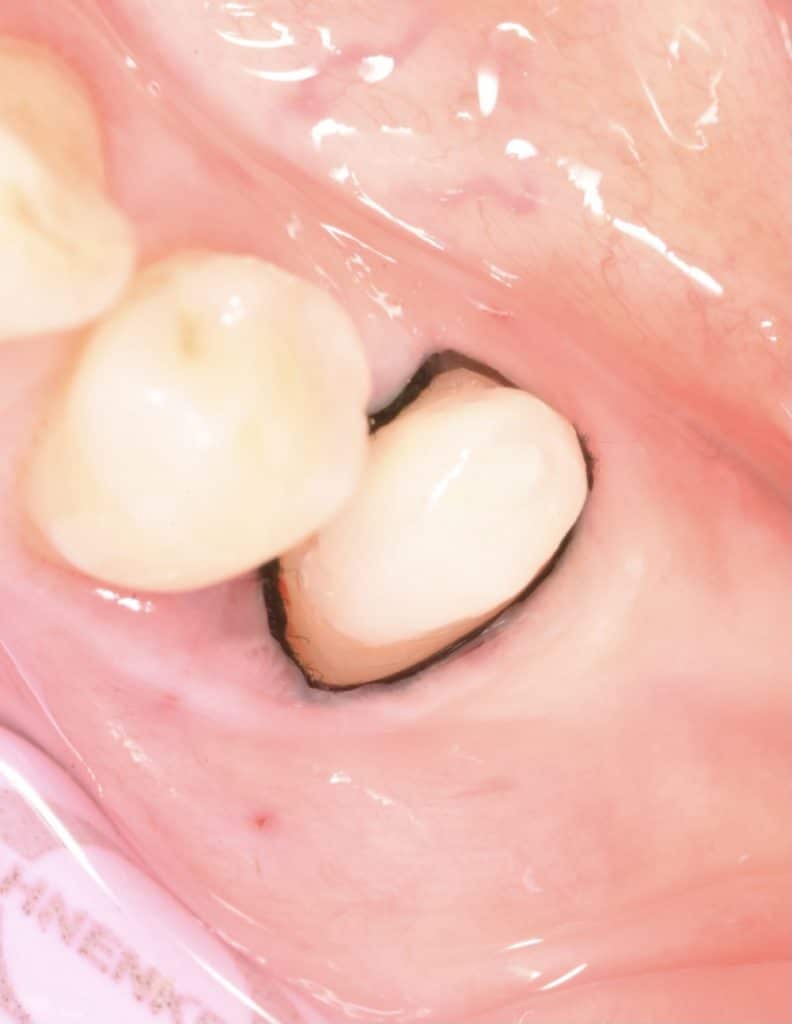

⛔️ zirconia crown cementation done with dual cure resin cement.

⛔️ follow up one month now and gingiva healthy.